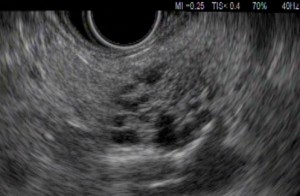

Endoscopic ultrasound (EUS) is an advanced endoscopic procedure specialized for the evaluation of various benign and malignant diseases involving the gastrointestinal tract and pancreatobiliary system using an ultrasound probe equipped on a flexible endoscope. Depending on the disease condition being evaluated, an EUS procedure usually takes about 20 to 40 minutes. Common conditions that can benefit from EUS are listed below (Table 1).

- Pancreatic cystic neoplasm